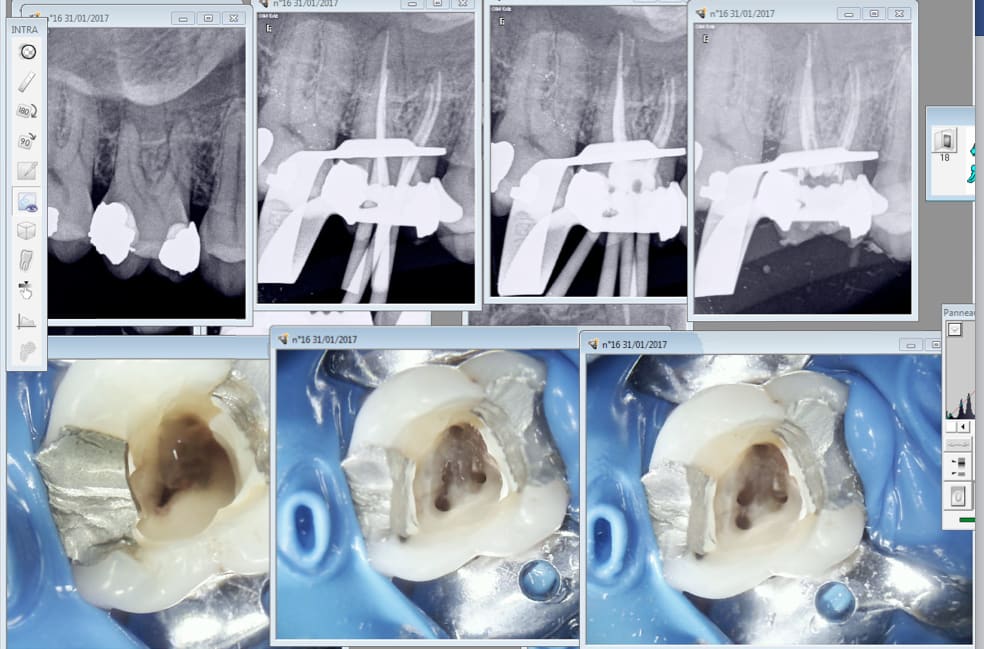

Non pour une fois pas besoin de les reprendre.

C'est sur on tire à pile ou face.

Face !

Fallait pas la garder vivante au départ. Quand la pulpe est blette elle est blette. Pas une goutte de sang à l'ouverture.

A votre avis en combien de temps j'ai réalisé cette endo ? Toujours pas de cathéthérisme manuel.

Et là, je compte 3/4 d'endo?

Vu que 1 seul canal était traité à moitié???😀😀😉

25min voir 35min max.